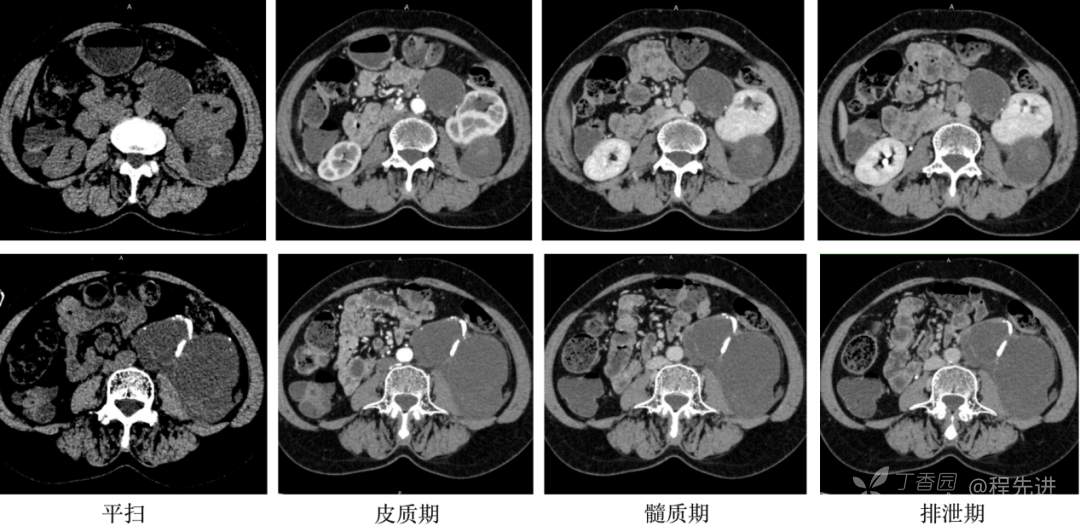

CT平扫+增强:

冠矢状位重建: